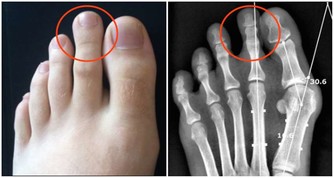

二、其他疾病對腎臟的損傷除了腎臟本身的疾病外,許多疾病在其展開進程中都可損傷腎臟,最後招致尿毒症的發作。多見的疾病有糖尿病、高血壓、系統性紅斑狼瘡、過敏性紫癜、高尿酸血症、多發性骨髓瘤、結節性多動脈炎、韋格內氏肉芽腫、系統性硬化、亞急性細菌性心內膜炎、肝硬化等。其中糖尿病和高血壓對腎臟的影響最多見,也最嚴重,現已成為尿毒症的重要原因。值得格外注意的是,人類免疫缺陷病毒(HIV,即艾滋病病毒)感染引起的尿毒症呈上升趨向,已經占到尿毒症病因的1%,但在年老人黑人中能存在與艾滋病相關性尿毒症的盛行。